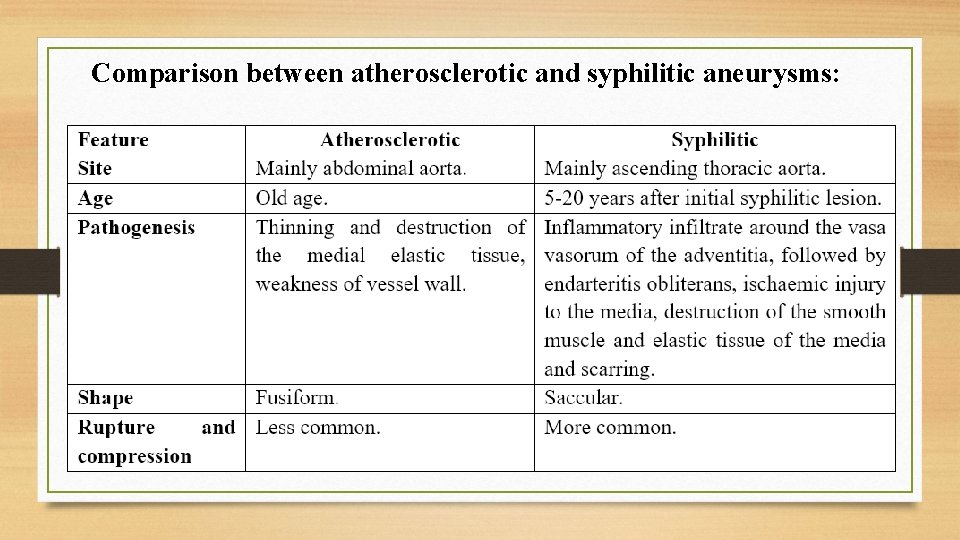

Comparison between atherosclerotic and syphilitic aneurysms: